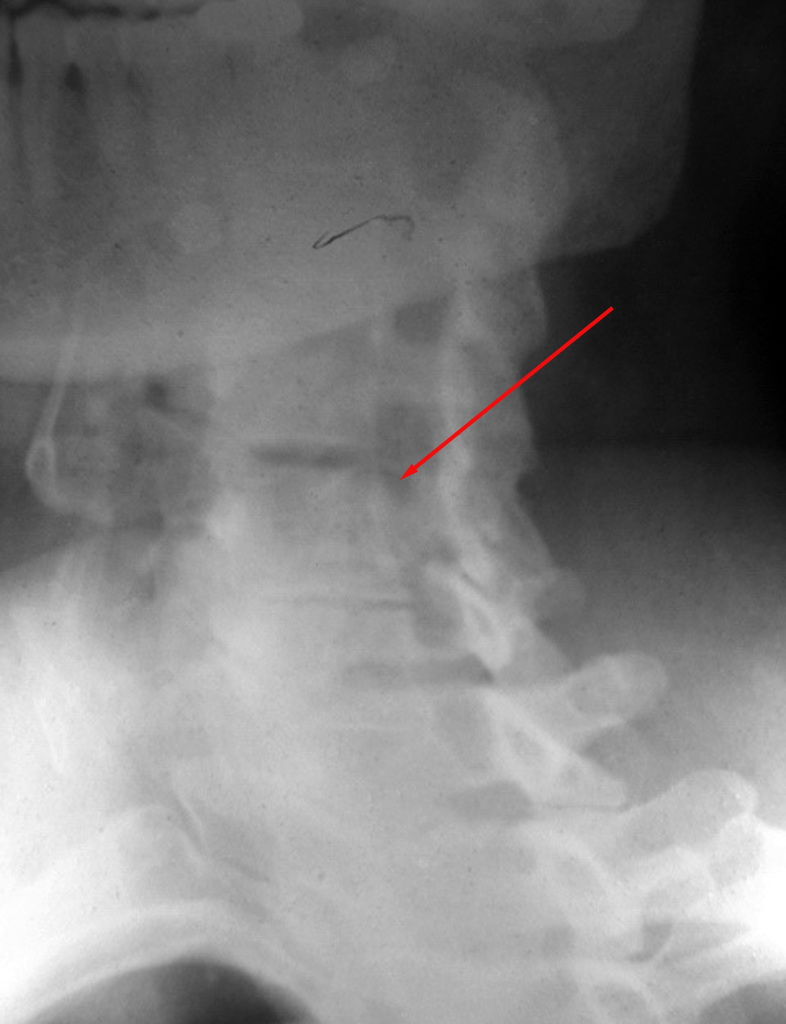

女.56,颈部及肩部疼痛半年,椎弓根及肩关节正常吗

未见异常! 从颈椎斜位观察:应为颈椎间盘病变

颈部看不清,肩部没问题。

颈部看不清,肩部没问题。最好做一个动力性颈椎侧位片看一下

颈椎,肩关节未见明显异常改变。颈椎正侧位呢?

体位不正,颈椎有退行性变